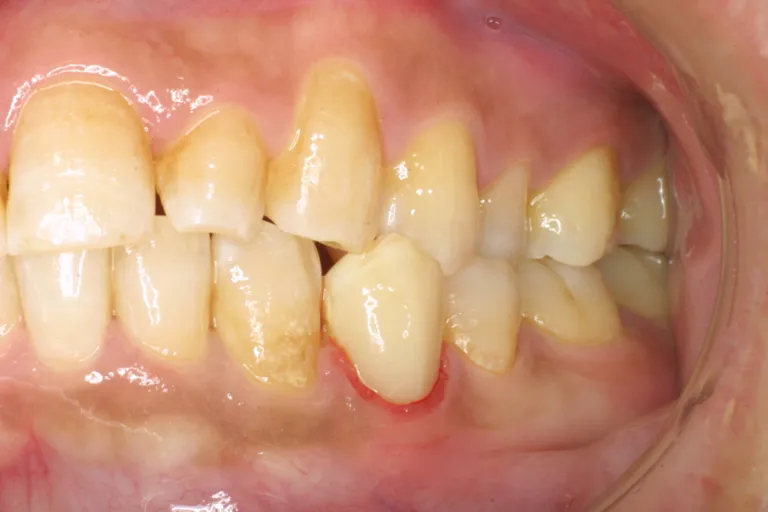

■術前・歯が広範囲に失われ治療履歴が多いため全体的に見直しす必要がありました

■術前の状態■

■術後・左下が新しく作った部分入れ歯です 部分入れ歯では残った歯に鈎(かぎ)をかけて支えます

■術後の状態■

歯が広範囲に失われ、しかもブリッジで治療しない場合や、ブリッジでの治療が困難な場合には、取り外し式の入れ歯を作ることになります。

総入れ歯では、土手の粘膜に吸着するように作りますが、部分入れ歯では、残った歯に鈎(かぎ)をかけて支えます。